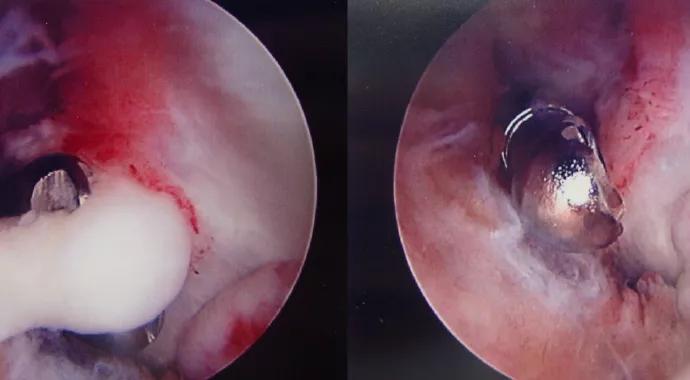

If a patient has acceptable flexion and lacks only extension, the release can be done either all arthroscopically or open via the lateral column or a medial over-the-top technique. We prefer an arthroscopic release (Figure 3) of the anterior elbow to gain extension, as it avoids tendon healing and minimizes postoperative scar formation.

Figure 3. Arthroscopic view of an elbow with abundant soft tissue adhesions (left). Arthroscopic lysis of adhesions (middle) and debridement (right).